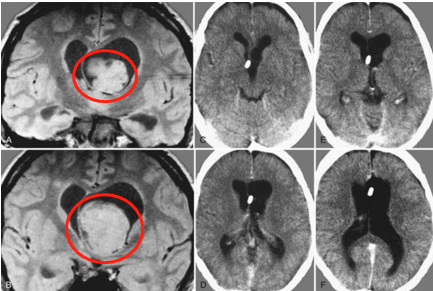

腦干間變型室管膜瘤手術(shù)、放療失敗,二次手術(shù)全切報(bào)告

簡(jiǎn)要病史:7歲男孩軒軒(化名),3年前出現(xiàn)步態(tài)不穩(wěn),惡心嘔吐。于北京行頭顱MR檢查,發(fā)現(xiàn)腦干腫瘤。當(dāng)時(shí)即在中國(guó)行開(kāi)顱腫瘤切除術(shù),術(shù)后癥狀無(wú)好轉(zhuǎn),術(shù)后開(kāi)始行質(zhì)子刀放射治療...